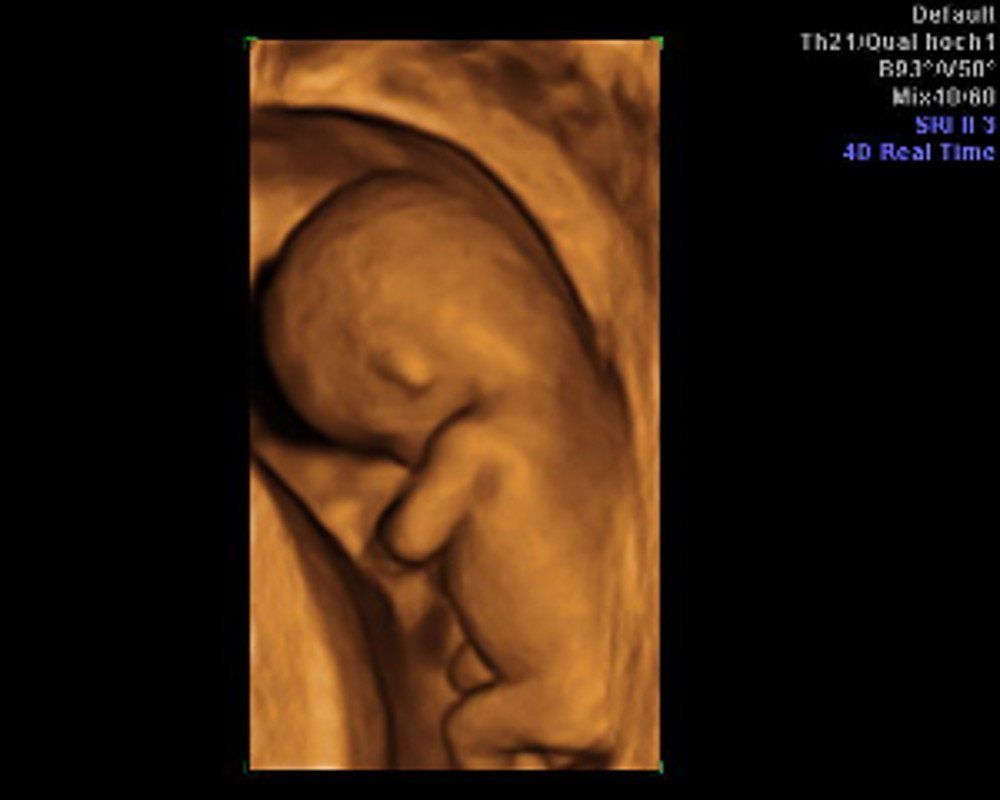

It is the target of the NT screening to discover an early and individual assessment of the likelihood of the occurrence of the Down syndrome. To this end, a special ultrasound screening of the neck of the foetus is carried out in the 12 to 14th week of pregnancy and is intensively scrutinised.